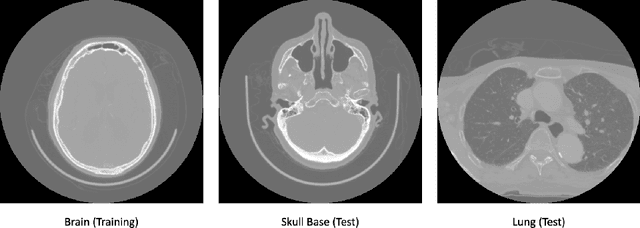

In the domain of medical image processing, medical device manufacturers protect their intellectual property in many cases by shipping only compiled software, i.e. binary code which can be executed but is difficult to be understood by a potential attacker. In this paper, we investigate how well this procedure is able to protect image processing algorithms. In particular, we investigate whether the computation of mono-energetic images and iodine maps from dual energy CT data can be reverse-engineered by machine learning methods. Our results indicate that both can be approximated using only one single slice image as training data at a very high accuracy with structural similarity greater than 0.98 in all investigated cases.